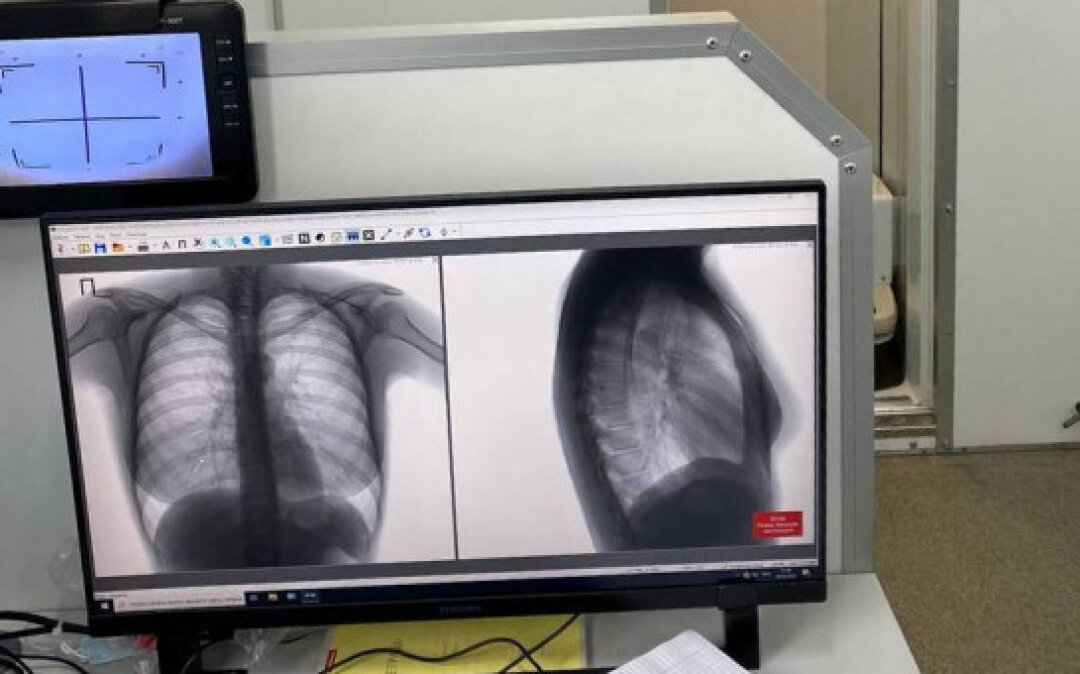

Если раньше флюорографическое исследование проводилось методом двойного чтения, чтобы исключить ошибки в скрининге, и флюорографический снимок смотрели два врача, то сейчас используется третье мнение – это мнение искусственного интеллекта. Сотрудники Областной туберкулезной больницы были одними из первых, кто начал применять эту технологию на практике.

«Искусственный интеллект анализирует флюрограммы, мамограммы и компьютерные томограммы, включая малодозные, – рассказала заведующая рентгенологическим отделением Ольга Лелянова. – Он видит очаговое образование, пневмоторакс, патологию плевры, патологию корня легкого и все это дело подчеркивает. Это облегчает работу, потому что открывая вот это «третье мнение», врач сразу видит, на что обратить дополнительное внимание. Это страхует нас от пропуска патологии, потому что позволяет дополнительно, так сказать, зацепиться, акцентирует наше внимание на каких-то патологических изменениях. Или изменениях, которые могут быть патологическими».

Компьютерный анализ снимков ускоряет диагностику, особенно при проведении массовых скринингов. Если же мнение специалиста и программы расходятся, то итоговое решение принимает врач. Система только заостряет внимание на отклонениях от нормы, а специалист решает, что это: погрешность из-за неправильной позы пациента, суммация теней или все же патологическое состояние.

В тестовом режиме система искуственного интеллекта запущена полтора года назад, в «боевом» работает уже год. Все снимки, которые выполнены в цифровом формате, проходят через нее. По словам Ольги Леляновой, к банку данных и системе анализа подключены почти все городские поликлиники и крупные больницы, тогда как в частном секторе врачи работают без поддержики искусственного интеллекта.